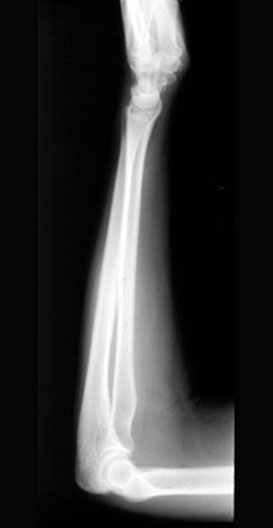

Lateral Forearm X-Ray

1. Ulna

2. Olecranon

3. Radius

4. Radial tuberosity

5. Trochlear joint